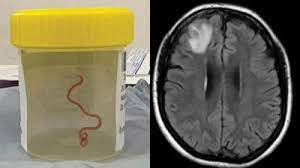

64-річній англійці, яка проживала в Австралії, зробили МРТ, яке показало, що в її мозку живе паразитичний круглий черв’як.

МРТ її мозку показало, що в ураженій правій лобовій частці живе рухливий гельмінт – паразитичний круглий черв’як.

Єдиним варіантом стало хірургічне втручання, і лікарі успішно видалили аскариду довжиною 8 см і діаметром 1 мм.